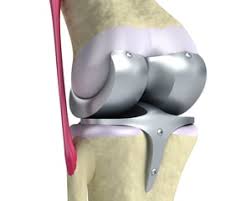

무릎 인공관절 수술, 왜 필요한가요?

무릎관절은 체중을 가장 많이 지탱하는 관절입니다. 나이가 들수록 연골은 점차 마모되고, 충격을 흡수하는 능력도 감소합니다. 이로 인해 통증, 뻣뻣함, 운동 제한이 생기며, 이런 증상이 악화되면 인공관절 수술이 필요해집니다.

퇴행성 관절염 외에도 류마티스 관절염이나 외상 후 관절 손상이 심각할 경우 수술이 권유되며, 수술을 통해 환자는 통증 없이 보행이 가능해지고 일상생활로 복귀할 수 있게 됩니다.